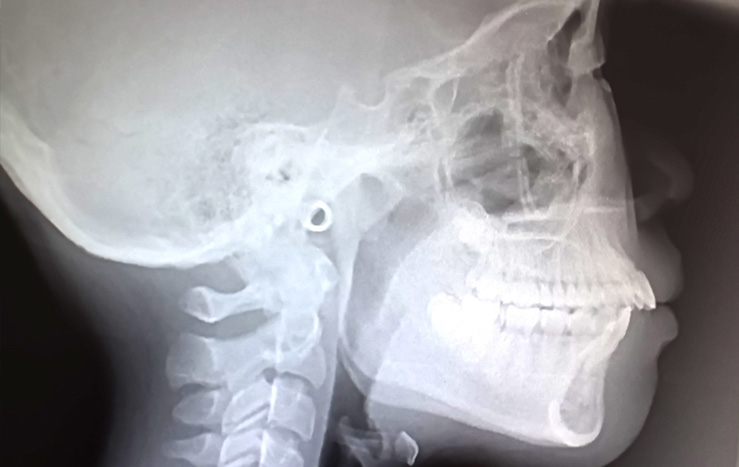

セファロレントゲン

top_feature_headline_bar

頭部を正面と側面から撮影することで顔の骨格を詳しく把握することができます。